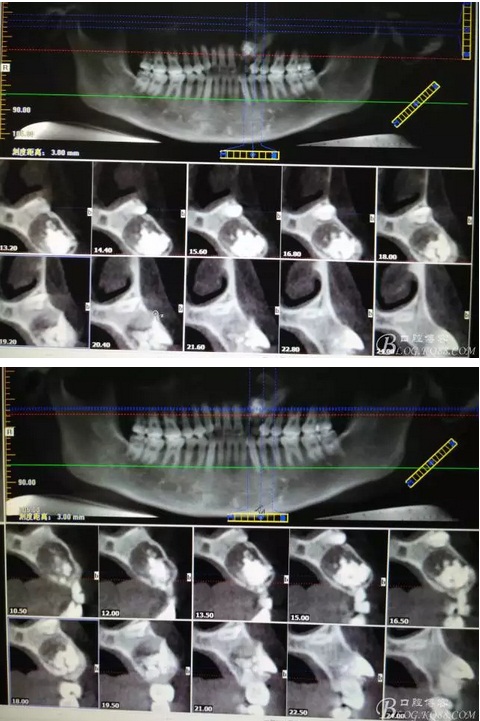

圖1。術前的CBCT影像檢查:22位于鼻底下方,23位于24、25的根方。左側乳Ⅱ、Ⅲ根方顯示囊性改變,囊腔內大量致密鈣化團塊,密度高。